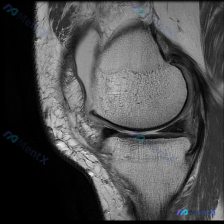

最近碰到一个有意思的读片病例,临床怀疑膝关节软骨异常,给了一张髌股关节轴位T1加权MRI,整理了一下分析思路分享给大家。 一、病例基本影像信息 这是单张膝关节髌股关节水平的轴位T1加权MRI扫描图: 1. 扫描层面:髌股关节水平,可见上方髌骨、下方股骨滑车沟的关节结构 2. 骨骼:股骨远端骨皮质完整...